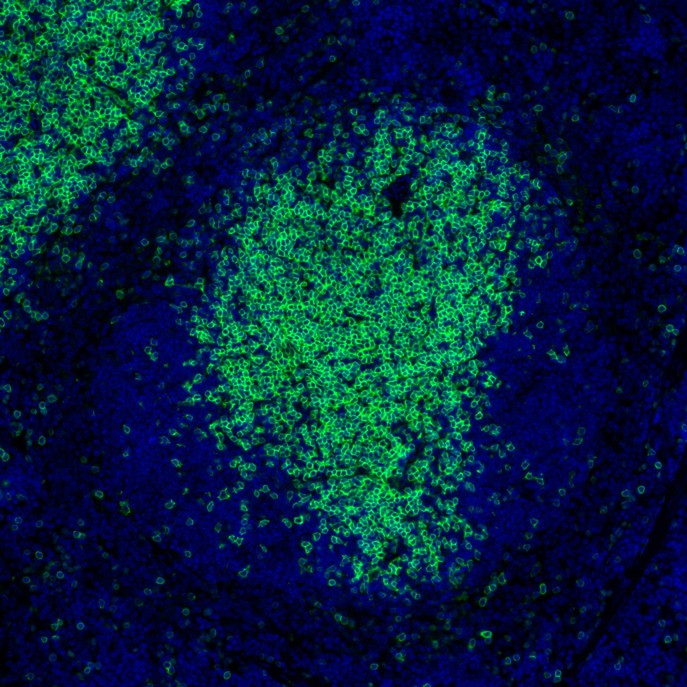

Catalog# HA722966

CD4 Recombinant Rabbit Monoclonal Antibody [PSH08-22]

mIHC